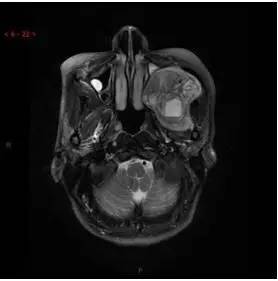

T1WI轴位

T2WI/FS轴位

T2WI/FS冠状位